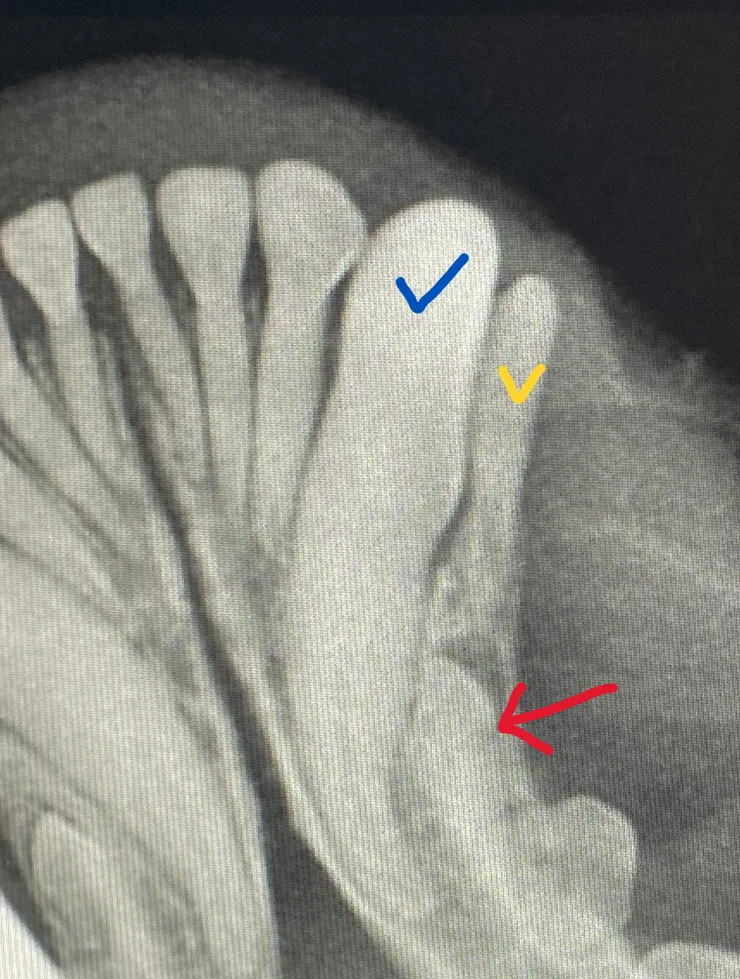

乳牙必須拔除,必須正視它的影響對,不能。或許看起來很可愛,但實際上殘留的乳牙不僅會造成牙周問題,關係到咬合狀況,有時候也會影響到正常恆牙的發育,簡單來說就是佔據別人的空間,讓恆牙長不出來被包覆在骨頭裡面,形成另一個更麻煩的問題:含牙囊腫 (Dentigerous cyst),這是一件很不舒服的事情,更需要依賴齒科X光與經驗豐富的操作,才能順利將包埋在骨頭裡面的恆牙拔除

無法順利掉下來的乳牙建議必須拔掉,然而拔乳牙也並非想像的這麼容易,一般我們將拔乳牙視為手術性的拔牙,意思就是必須切開牙齦,打磨掉部分骨頭才能順利拔乾淨,因為乳牙的牙根通常都十分的細長,一個不小心是有機會拔斷的喔,因此建議拔乳牙時尋找具備齒科x光的醫院進行確認,避免沒有拔乾淨的問題。